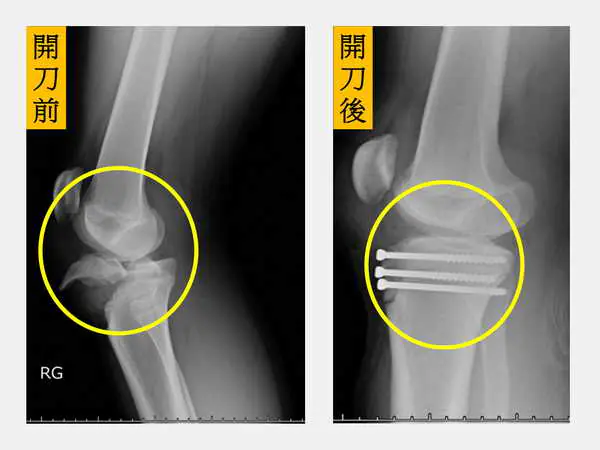

圖二:【左圖】林小弟的右腳膝蓋近端脛骨骨折合併生長板受損(圓圈處);【右圖】經安排骨折復位固定手術後(圓圈處),復原良好。

李祥安說,此類骨折的治療選擇包含保守治療以及手術治療。當骨折碎片沒有位移時,可以考慮採取石膏固定維持膝關節伸直約四週的時間,隨後可以使用膝關節活動支架保護,在醫師評估許可的範圍內活動復健至骨折完全癒合。當骨折有明顯位移,尤其是骨折有裂到膝關節裡面時,藉由手術將關節面恢復平整是必要的。

至於骨材的選擇,可根據患者的年齡而定,若小於10歲生長板尚未閉合的兒童,建議使用平滑鋼針固定以避免生長板造成進一步的破壞,若為青少年、骨齡將近成熟的病人,則可以使用螺釘固定,固定效果更強。